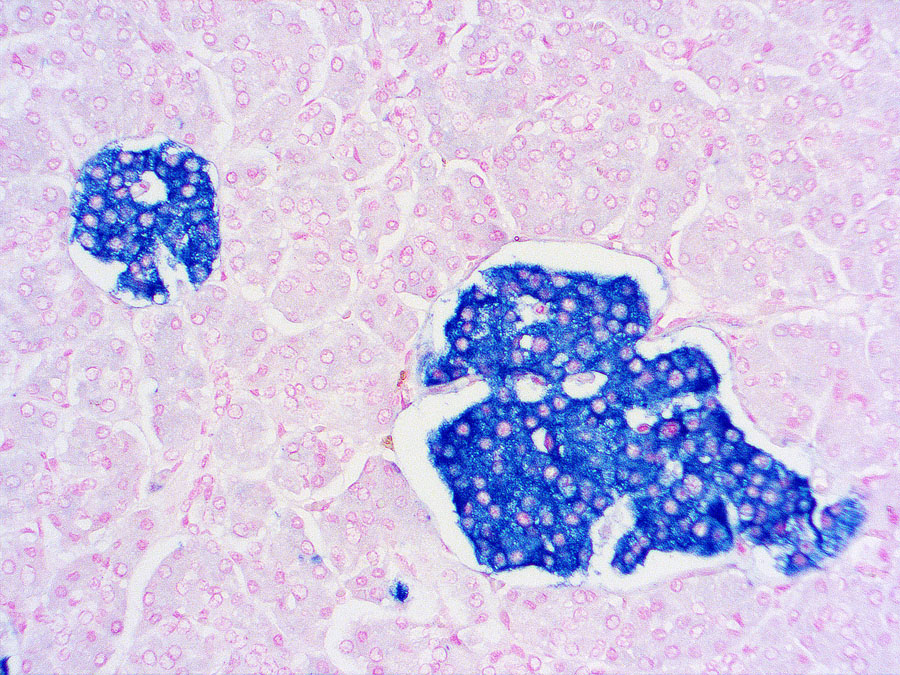

IHC-P analysis of human pancreas tissue using GTX79435 Synaptophysin antibody [SP11] (ready-to-use).